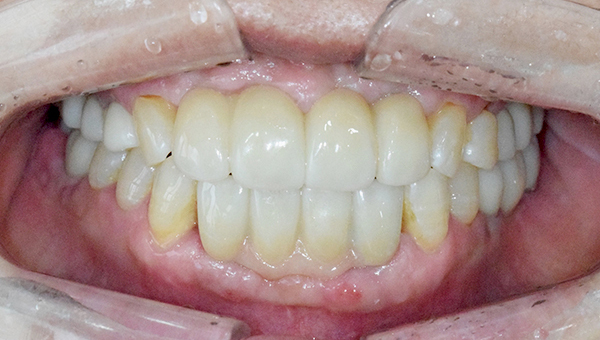

박*수 임플란트 시술 사례

전체 임플란트

20**.**.**

치료 전

치료 후